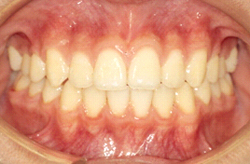

16歳0ヶ月の写真です。美しい歯並びになっており、咬みあわせも良い状態になりました。前歯が3本しかありませんでしたが、3本抜歯をすることで、左右対称な歯並びになりました。

- 治療方法

- 下顎右側側切歯の先天欠如を伴う過蓋咬合症と診断し、マルチブラケット装置にて上顎両側第一小臼歯、下顎左側第一小臼歯を抜去して治療